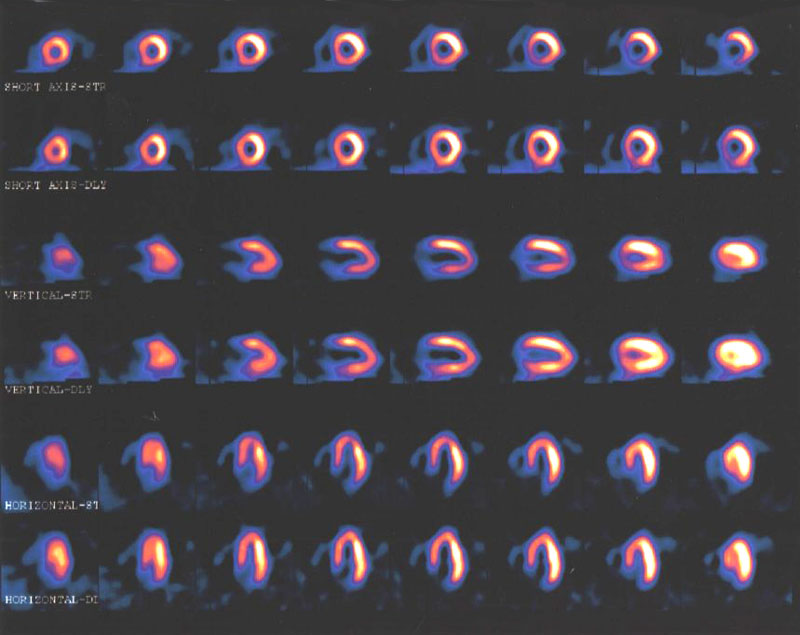

Alternativas menos invasivas para el diagnóstico de enfermedad coronaria

En pacientes con sospecha de enfermedad coronaria, la evaluación con resonancia magnética o gammagrafía de perfusión miocárdica permite reducir las angiografías innecesarias. JAMA, 29 de agosto de 2016